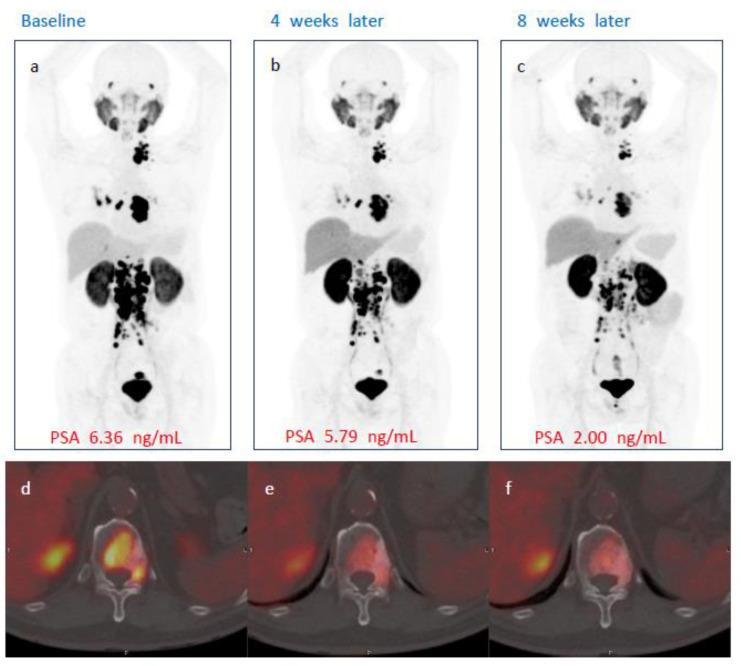

[Lu]Ludotadipep, which enables targeted delivery of beta-particle radiation to prostate tumor cells, had been suggested as a promising therapeutic option for mCRPC. From November 2020 to March 2022, a total of 30 patients were enrolled for single dose of [Lu]Ludotadipep RPT, 6 subjects in each of the 5 different activity groups of 1.9 GBq, 2.8 GBq, 3.7 GBq, 4.6 GBq, and 5.6 GBq. [Lu]Ludotadipep was administered via venous injection, and patients were hospitalized for three days to monitor for any adverse effects. Serum PSA levels were followed up at weeks 1, 2, 3, 4, 6, 8, and 12, and PSMA PET/CT with [F]Florastamin was obtained at baseline and again at weeks 4 and 8. The subjects required positive PSMA PET/CT prior to [Lu]Ludotadipep administration. Among the 29 subjects who received [Lu]Ludotadipep, 36 treatment emergent adverse events (TEAEs) occurred in 17 subjects (58.6%) and 4 adverse drug reactions (ADRs) in 3 subjects (10.3%). Of the total 24 subjects who had full 12-week follow-up data, 16 (66.7%) showed decrease in PSA of any magnitude, and 9 (37.5%) showed a decrease in PSA by 50% or greater. A total of 5 of the 24 patients (20.8%) showed disease progression (PSA increase of 25% or higher from the baseline) at the 12th week following single dose of [Lu]Ludotadipep. These data thus far suggest that [Lu]Ludotadipep could be a promising RPT agent with low toxicity in mCRPC patients who have not been responsive to conventional treatments.